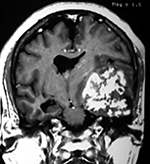

EJEMPLO DE CASO CLÍNICO (9)

Paciente masculino de 34 años de edad, quien presenta crisis convulsivas parciales motoras de brazo y hemicara derecha, secundariamente generalizadas, posteriormente hemiparesia 4/5 para hemicuerpo derecho.

La TAC muestra un área hiperdensa a nivel frontal izquierdo heterogénea que no refuerza con medio de contraste.

LA RMN muestra una lesión bien circunscrita frontal parasagital izquierda con edema perilesional, hiperintensa en T1 y T2, de contenido sólido y quístico, con poca captación del medio de contraste.

Se realizó craneotomía frontal para abordaje interhemisférico anterior.

Se realiza resección total de la lesión de contenido hemático oscuro-verdoso, consistente en un angioma cavernoso. La RMN postoperatoria se observa solo la brecha quirúrgica sin evidencia de lesión.

En el postquirúrgico el paciente desarrollo síndrome frontal lateral, que se controló con Risperidona y remitió después de tres semanas, las crisis convulsivas remitieron y el medicamento se disminuyó de manera paulatina (figs. 4 y 5).

Figura 4:

Imágenes prequirúrgicas y postquirúrgicas de lesión multiloculada del caso 9.